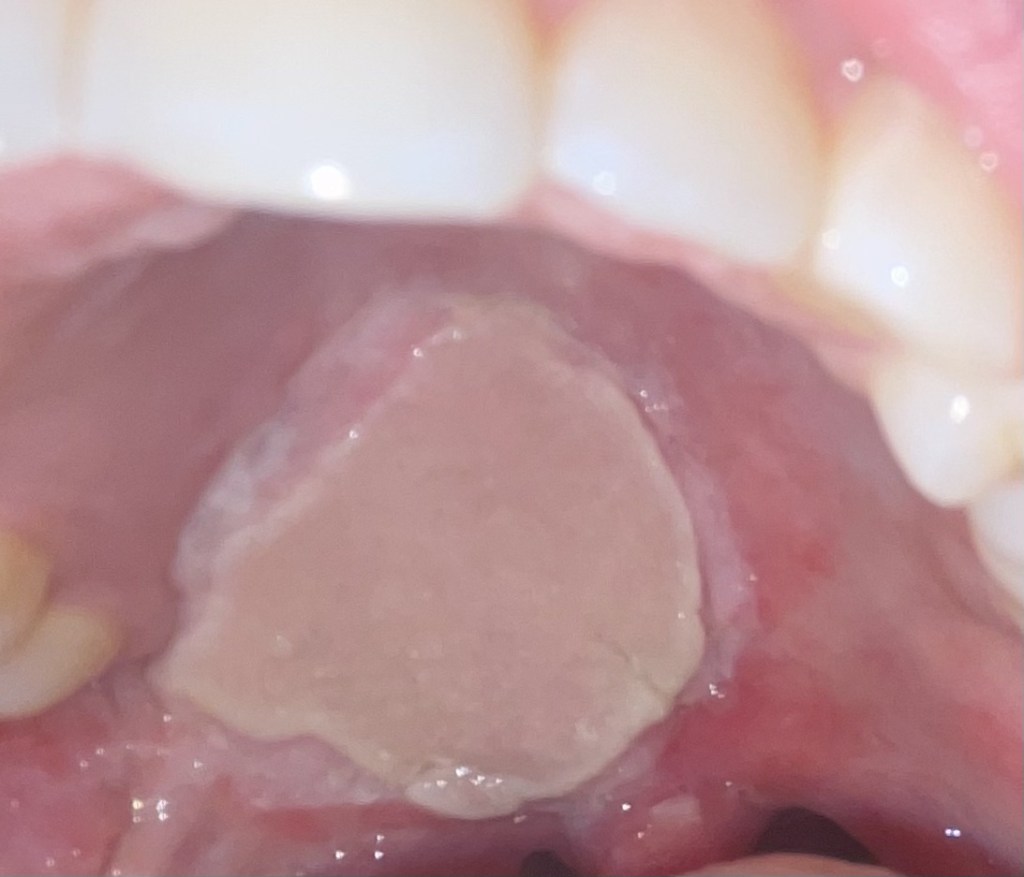

Here is the new skin in my mouth. (Before and after healing + radiation).

I have some hair’s starting to grow there. My surgeon mentioned laser treatment if it gets too crazy.